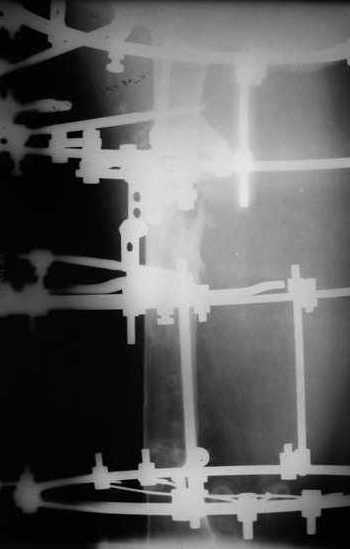

Re: Proximal femoral shaft nonunion + osteomyeliti

Вчера сделали рентгенограммы бедра нашему пациенту. Угловое смещение нам удалось исправить.

Сейчас проводим дистракцию (2 см).